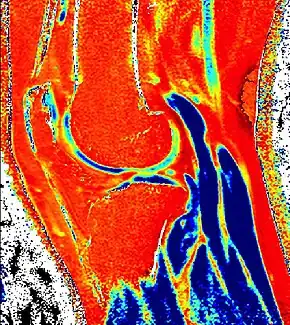

dGEMRIC T1 Map of knee cartilage | |

Delayed gadolinium-enhanced magnetic resonance imaging of cartilage or dGEMRIC measures the fixed-charge density and relative proteoglycan content of articular cartilage using the spin-lattice relaxation time or T1 relaxation time.[1] Current research is investigating the clinical application of dGEMRIC as a quantitative tool for monitoring cartilage function in diseased or repair cartilage.[2]